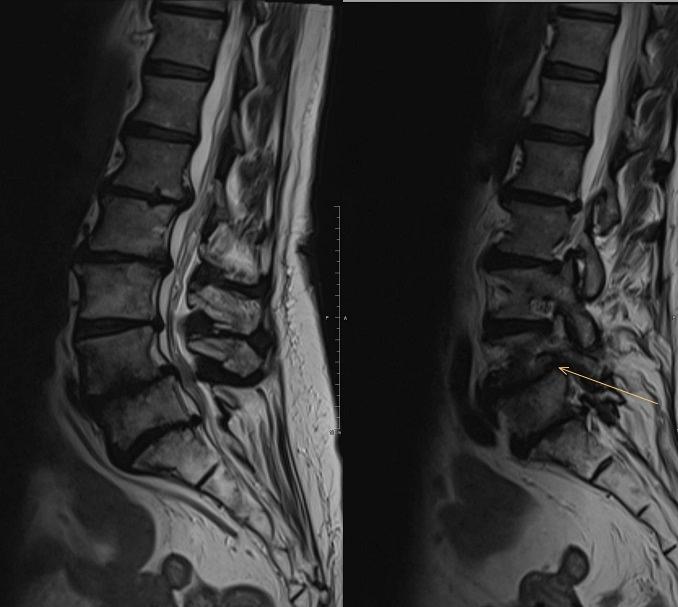

Dit artikel beschrijft hoe de klinische besluitvorming verloopt bij specifieke en aspecifieke lage rugpijn vanuit orthopedisch en fysiotherapeutisch perspectief. Bij veel klachten die een fysiotherapeut ziet, zijn er altijd meer variabelen die tegelijk een rol spelen. Voor patiënten met lage rugpijn in Nederland spelen deze epidemiologische variabelen mee: toename van vergrijzing, toename in co-morbiditeiten, toename in overgewicht, toename in problemen met mentale welzijn. Het biopsychosociaal model is een gevestigd model. Bij een juiste toepassing ondersteunt dit model een brede kijk op gezondheid waarbij al deze variabelen worden meegenomen. Fysiotherapeuten hebben de kennis, tijd en kunde om in de regio te ontzorgen. Orthopedisch chirurgen en huisartsen hebben baat bij een goed functionerend netwerk aan deskundige fysiotherapeuten. Dit artikel beschrijft de samenwerking tussen fysiotherapie en orthopedie ten aanzien van complexe lage rugpijn aan de hand van drie casussen. De conclusie is dat als de fysiotherapeut en orthopedisch chirurg dezelfde taal spreken en hetzelfde doel nastreven, dit bijdraagt aan het succes van de aanpak van dit probleem.

• kent u de huidige behandelmethodes voor chronische a-specifieke lage rugpijn, centrale kanaalstenose met neurogene claudicatio, en spondylodese